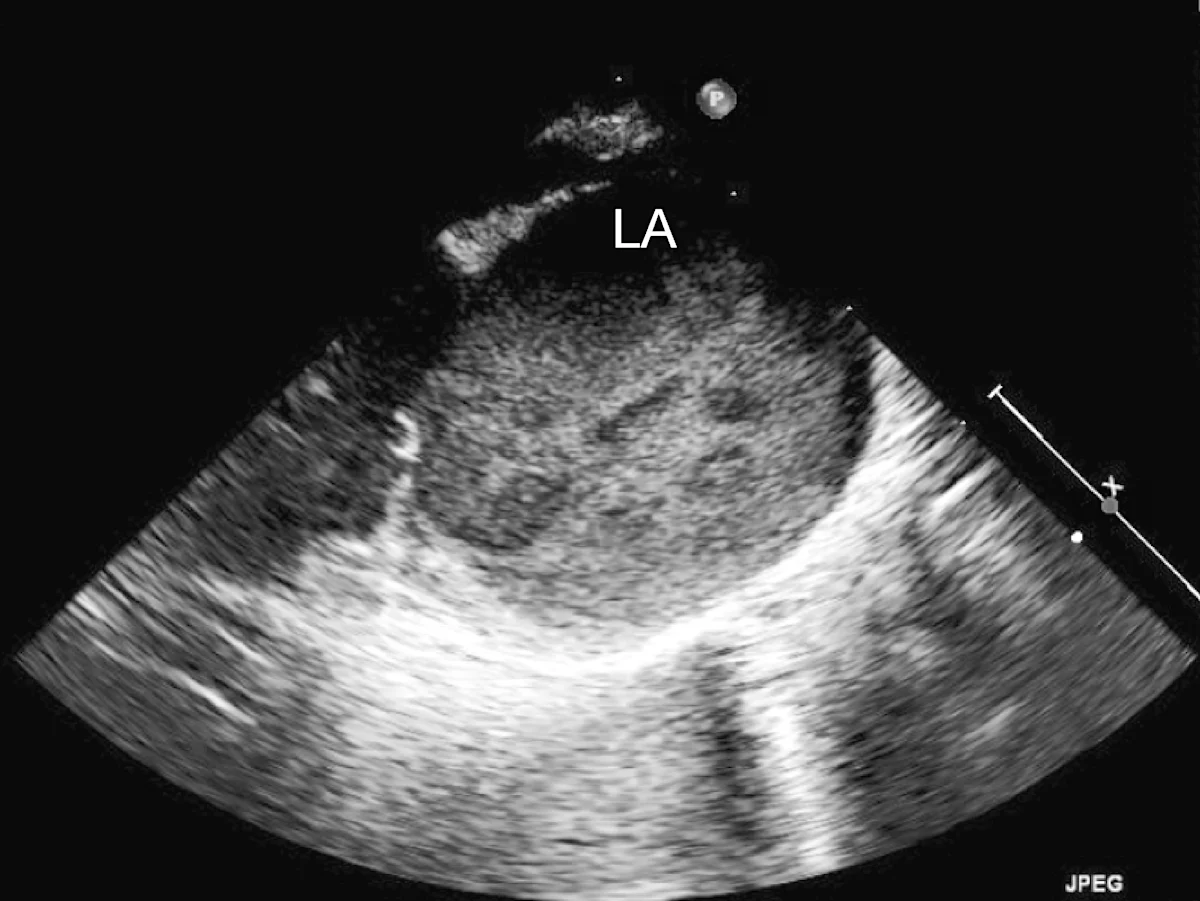

Marked left atrial enlargement was present on echocardiography after stabilization and pain management (see Treatment). A formed thrombus was apparent within the left auricle (Figure 4) and spontaneous echo contrast or smoke was present within the left atrium (Figure 5). This spontaneous echo contrast is often seen with marked chamber dilation and blood stasis; although its presence is associated with an increased risk for thrombus formation, it is not a result of a formed thrombus. Thickening of the left ventricular walls was also noted (Figure 6), which is consistent with underlying hypertrophic cardiomyopathy.

Right parasternal oblique long-axis echocardiographic view showing spontaneous contrast smoke within the left atrium (LA)

Echocardiography helped definitively diagnose underlying cardiomyopathy and the likely origin of the thrombus. The hypertrophied left ventricular wall is consistent with hypertrophic cardiomyopathy if certain conditions (eg, hyperthyroidism, hypertension) are ruled out. The markedly enlarged left atrium and spontaneous contrast indicate high risk for thromboembolic complications. In Watson, a formed thrombus within the left auricle was detected, which further supported a diagnosis of feline arterial thromboembolism.